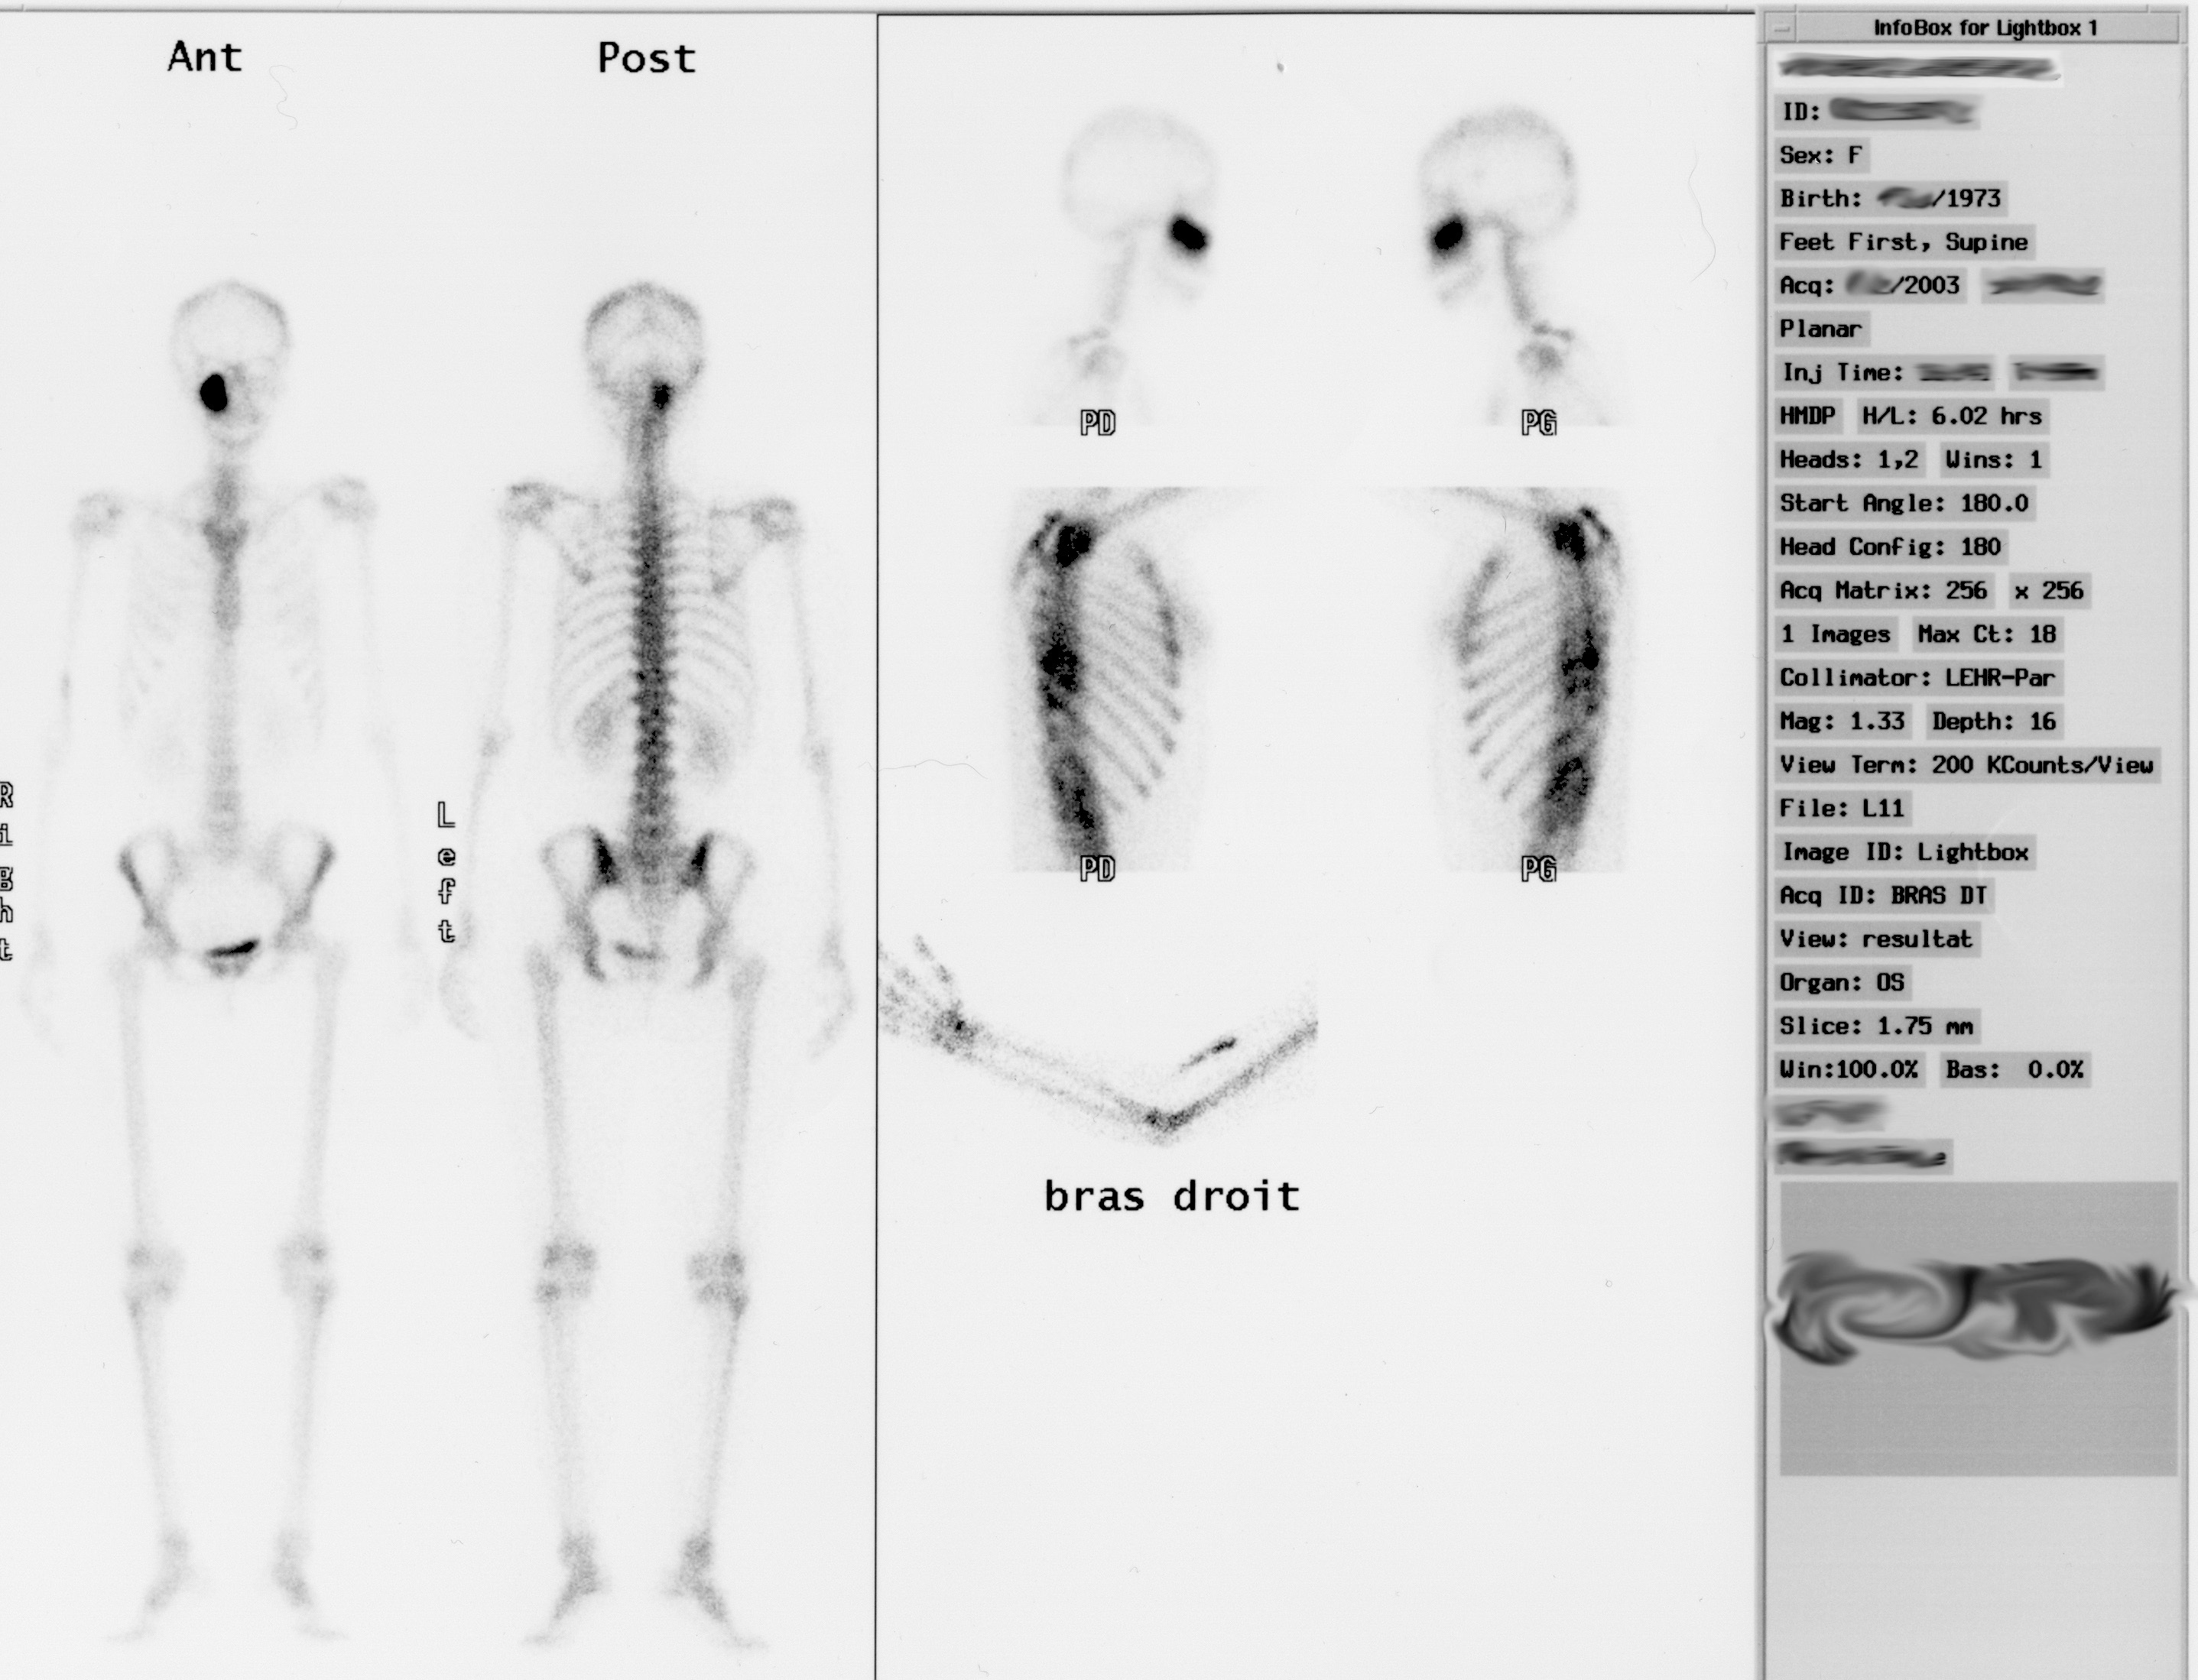

Bild

JPG

Ganzkörper-Szintigramm, Foto

Big Bang 8